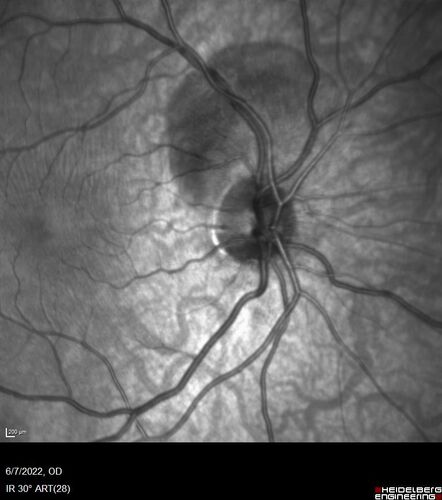

Traumatic Peripapillary Subretinal Hemorrhage

16 year old hit in eye with finger during basketball. Vision is 20/25 and there is a peripapillary hemorrhage.